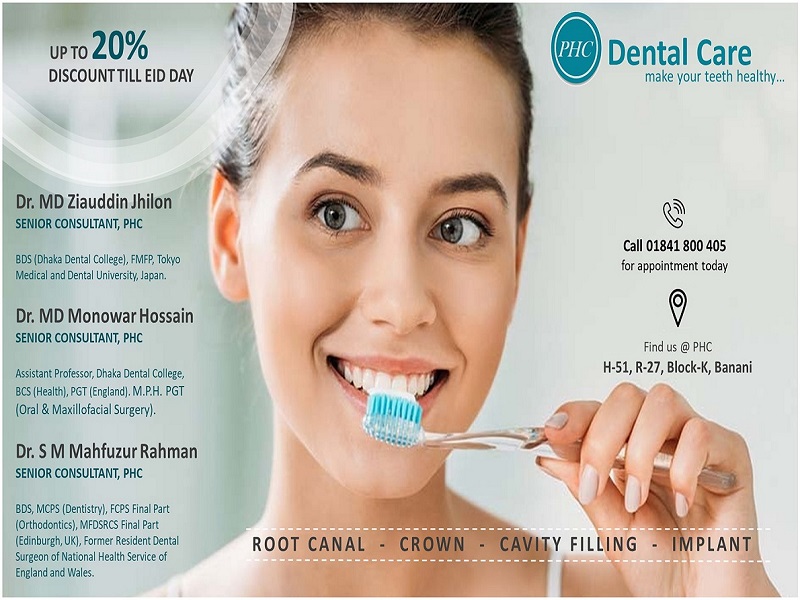

Dental

Dental

It is the desire of everyone to stay healthy until before their time in the earth. Though such wish is a reasonable one, to make it true, we must take utmost importance in maintaining ourselves salubrious over the whole period of time through regular exercises, proper diet and hygiene. Along with our body, the one other significant part that must be taken care of...

Dr. Md. Ziauddin Jhilon

BDS (Dhaka Dental College) FMFP, Tokyo Medical and Dental University, Japan Specialized in Post Surgical Prosthetic Rehabilitation Specialized in Implantology Specialized Consultant of Prosthetic and General Dentistry